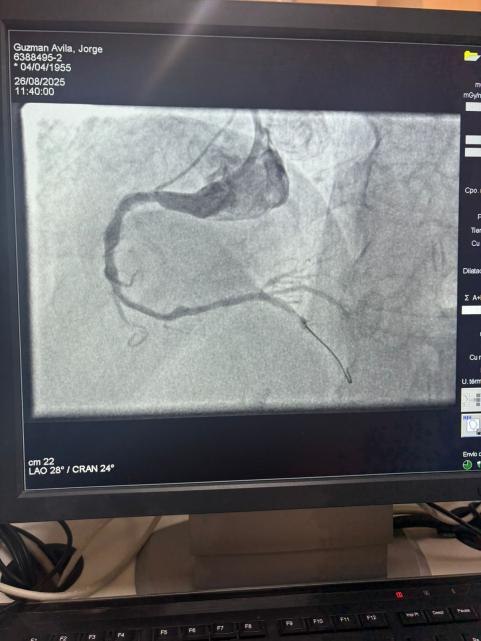

LEPU

チリのソテロデルリオ病院からの注目すべき事例を共有できることを誇りに思います。マルティンバルデベニート博士は、ベススクラック冠状動脈IVLバルーン希釈カテーテルシステムを使用して、右冠状動脈の重度の石灰化病変 (最初の曲線) の治療に成功しました。

この手順は、石灰化領域に効果的にひびが入り、血管の流れが回復し、優れた結果を達成しました。 これは、複雑な冠状動脈石灰化のための高度なソリューションへのグローバルアクセスを拡大する上でのもう1つのマイルストーンを示しています。

処置前画像と処置後の血管造影画像の比較は、当社のIVL技術の重大な臨床的影響を明確に示しています。